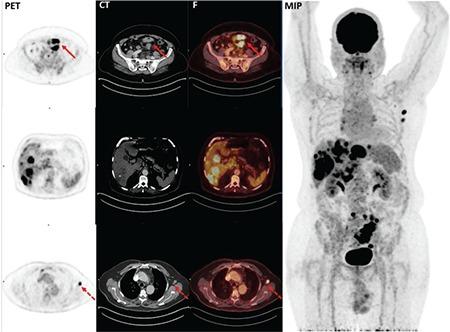

F-FDG PET/CT与KRAS突变在结直肠癌中的预后价值

The Prognostic Value of F-FDG PET/CT and KRAS Mutation in Colorectal Cancers.

Prognostic effect of KRAS mutation and side of tumor in colorectal cancer is a highly controversial subject. Therefore, we evaluated the association between FDG uptake pattern in F-fluoro-2-deoxy-glucose positron emission tomography/computed tomography (F-FDG PET/CT) imaging and KRAS mutation and tumor localization in patients with a diagnosis of colon cancer and assessed the effects of these three factors on prognosis and survival.

METHODS

Eighty-three patients with colorectal cancer were retrospectively included in this study. F-FDG PET/CT study was performed for pretreatment staging. The maximum standardized uptake value (SUV) of the primary tumor and survival data of patients were compared between groups. KRAS mutations were detected with the help of real-time Polymerase Chain Reaction technique through genomic DNA extracted from paraffin-embedded tumor tissue blocks. Tumor lesions with potential KRAS mutations were classified as mutant KRAS and wild type.

RESULTS

Twenty five patients were female while 58 were male. The mean age of the patients was 59.8±11.3 years. Mean follow-up was 35.5±18.9 months. Primary tumor was localized in the left colon in 83.1% of patients and in the right colon in 16.9%. KRAS mutation was detected in 54.2% (n=45) of patients. Mean SUV of patients with primary tumor was estimated to be 21.1±9.1 (range= 6.0-47.5). Mean tumor SUV of patients with a KRAS mutation (24.0±9.0) was found to be significantly higher than those without KRAS mutation (17.7±8.2) (p=0.001). Mean survival was significantly shorter in patients with locoregional nodal metastasis than in patients without locoregional nodal metastasis as well as in patients with distant nodal metastasis than in patients without distant nodal metastasis and in patients with organ metastasis in initial PET/CT than in patients without organ metastasis. Also, mean survival was nearly statistically-significantly shorter in patients with tumors located in left colon (34.2±19.4) than in right colon (43.2±14.6) (p=0.059). However, we found no significant impact of KRAS mutation on survival.

CONCLUSION

In our study, we found that tumor localization had no significant effect on prognosis in patients with colon cancer. On the other hand, FDG uptake was observed to be higher in the presence of KRAS mutation and it was concluded that coexistence of KRAS mutation with higher SUV is a negative prognostic factor.